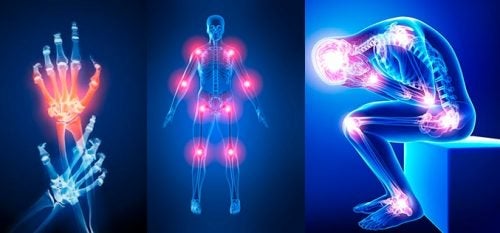

Sirke, zencefil ve biber karışımı ile diz, kemik ve eklem ağrısına son: Dudak uçuklattı! Adeta çakı gibi böyle oluyor

İltihaplı eklem romatizması (Romatoid artrit), diz, kemik ve eklem ağrısı çekenler için etkili bir ev yapımı karışım. İltihaplı romatizma tedavi edilmediğinde eklem, göz, karaciğer, beyin ve böbreği etkiliyor. İltihaplı eklem romatizması olanlar dikkat! ltihaplı romatizma hastalarının sayısı artıyor mutlaka deneyin..